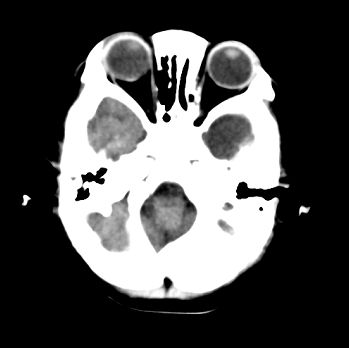

以下是引用22222222在2008-6-9 21:03:00的发言:[br]病灶周围见脑组织包绕,上部可见等或稍高密度壁环绕,壁且见小点钙化-----考虑皮样囊肿或表皮样囊肿可能,但侧脑室颞角内病灶不排除.